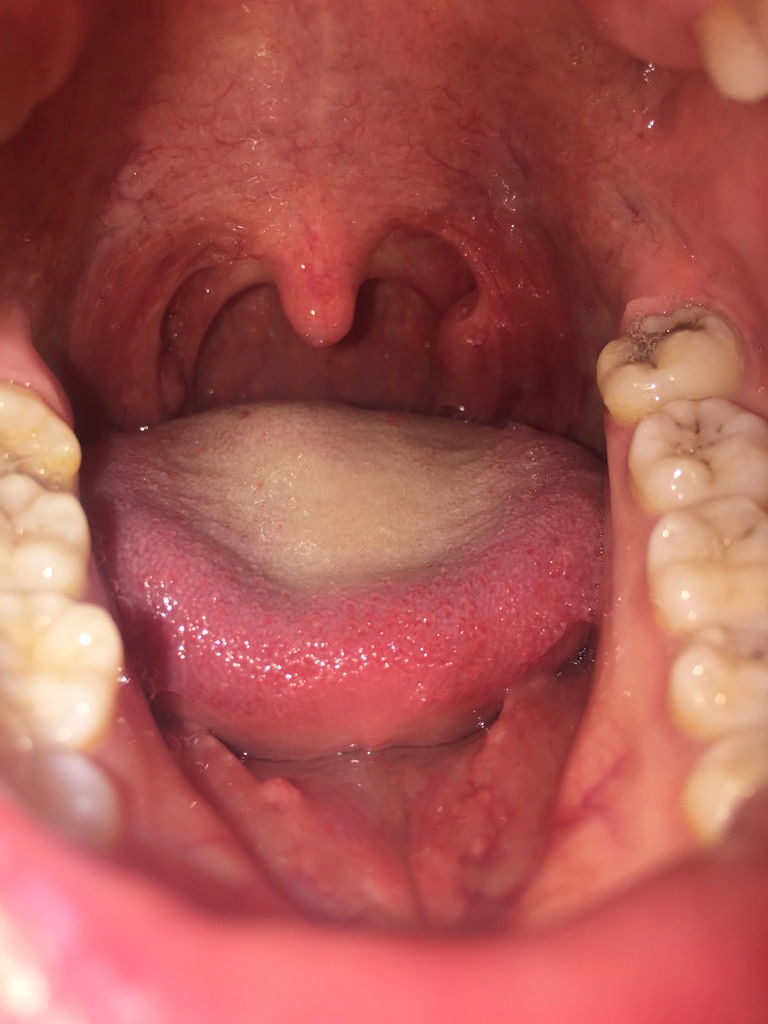

孕妇怀孕七个月喉咙长了白色的颗粒在肉里面,说话很疼,难受,请问医生

喉咙上面长了一颗白色的东西,长了大概有几个星期了,不疼不痒,能看

喉咙旁边长了一个白白的东西怎么办? 不会痛,刷牙有异物感

嗓子里面有点别扭不是很疼 照镜子看到喉咙旁边有两个白色的东西 很

喉咙里长了个像米粒一样大的白点,不痛不痒,就有

男孩六周岁,镜下所见,悬雍垂水肿,咽部粘膜充血,咽后壁淋巴滤泡增生

喉咙扁桃体旁边起了个乳白色米粒状的东西,不痛不痒,有异物感,有三四

囊肿常呈半透明的小泡,状似水泡,可呈蓝紫色或粉红色,逐渐增大,大多为

问:急性咽炎,怎么治疗,悬雍垂水肿